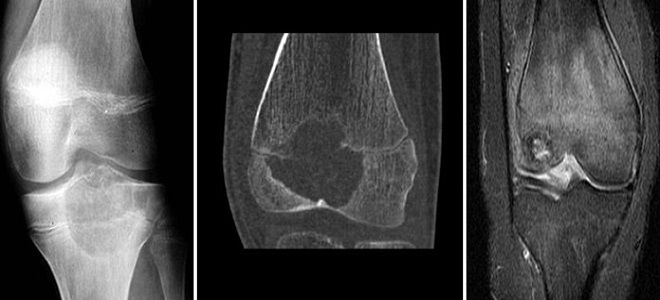

Рентгеновские снимки доброкачественных опухолей костей